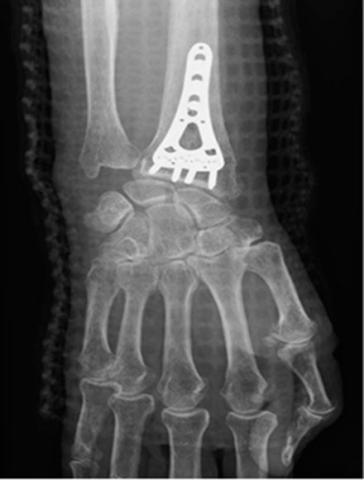

We included 61 patients with a mean age of 59 years (range: 19-84 years), 71% were female. A total of 23 patients were operated with open reduction and internal fixation with a volar plate. All patients answered the QuickDASH questionnaire at their first and last control (after an average of nine and 44 days, respectively) and 44 patients answered the QuickDASH questionnaire at 44 + 1 days. We measured the time used to complete the questionnaire at the first follow-up with the first 15 patients. At this point, none of the patients had ever

answered the QuickDASH before. The mean time employed to answer the questionnaire was four (range: 2-11) minutes. Furthermore, we received no questionnaires with missing items at any follow-up. Cronbach’s alpha was 0.96, displaying internal consistency from the total patient inclusion. The test-retest reliability was tested with 44 patients returning the questionnaire after the last follow-up and showed an intra-class correlation coefficient of 0.94 and a difference of mean of 0.39 (95% confidence interval: 0.13-0.91; p > 0.05) (Figure 1). We found a high correlation with the domains of Pain and Physical mobility which underpins the validity of the questionnaire (Table 1). Additionally, we found no floor or ceiling effect at either follow-up. Sum score at the first follow-up was 50.3, and at the last follow-up it was 24.1 (p < 0.05). The effect size was 1.1.